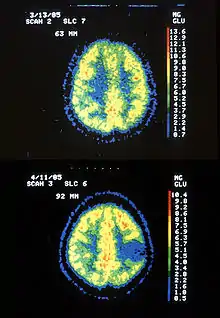

- Friedreich's ataxia: Manifestation: Local cerebral metabolic activity is increased extensively as the disease progresses.[3]

- ↑ Gilman; et al. "Cerebral Glucose Hypermetabolism in Friedreich's Ataxia Detected with Positron Emission Tomography" (PDF). Annals of Neurology. American Neurological Association. Retrieved 29 November 2012.